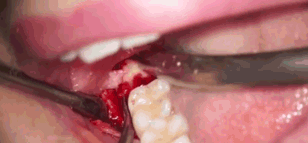

所以赶紧贴心地给他发了拔智齿的GIF

前

方

高

能